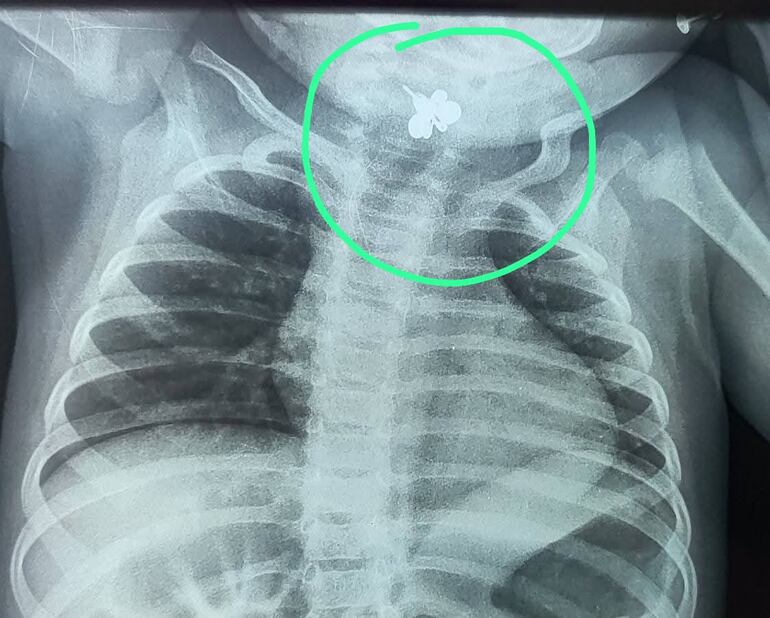

Finalmente, el estudio de imagen, reveló el diagnóstico: un arito estaba profundamente atascado en la faringolaringe y fue sometida a un procedimiento.

Los médicos señalan que fue difícil, delicado, tenso, “de esos que te obligan a poner alma, técnica y templanza al mismo tiempo”.